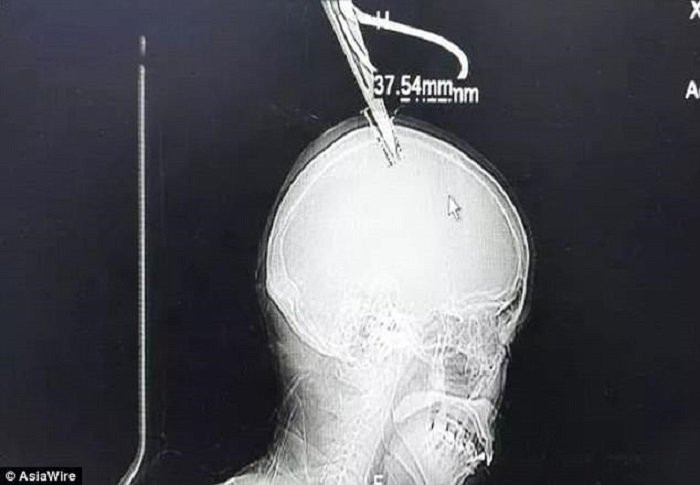

Shen cho biết không có ai ở nhà vào thời điểm xảy ra sự cố. Lưỡi kéo lún sâu vào đầu Shen khoảng 3,8 cm và đã chạm đến não.

Lưỡi kéo đâm sâu khoàng 4 cm và đã chạm đến não bộ.